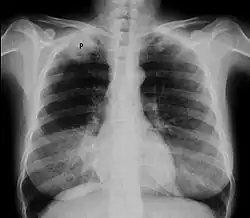

Chest X-ray showing a Pancoast tumor (labeled as P, non-small cell lung carcinoma, right lung), from a 47-year-old female smoker. | |